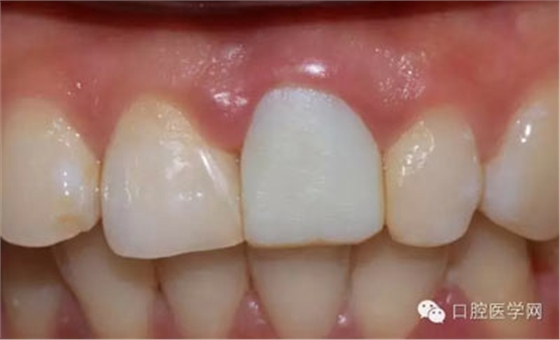

檢查:21金屬烤瓷冠修復(fù),顏色及形態(tài)與鄰牙不協(xié)調(diào),牙齦有輕微發(fā)黑,扣痛(-)、松動(dòng)度(-);11近中鄰面齲壞

術(shù)前照